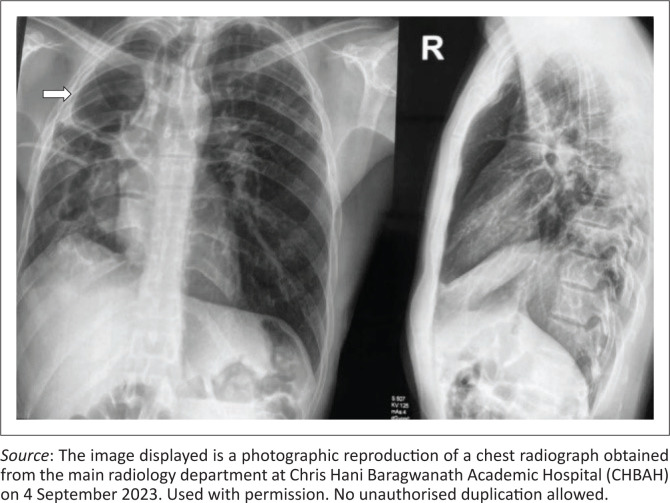

Intercostal artery-to-pulmonary artery fistula is an extremely rare variant of systemic artery-to-pulmonary artery fistulas (SA-PAFs). A case of a 38-year-old man presenting with clinically significant haemoptysis secondary to an intercostal artery-to-pulmonary artery fistula in the setting of post-pulmonary tuberculosis (TB) bronchiectasis is described. The fistulae were successfully treated with endovascular coils.

Contribution: This case report illustrates an intercostal artery-to-pulmonary artery fistula associated with post-primary tuberculosis bronchiectasis, highlighting its multimodal radiological features and successful endovascular treatment.